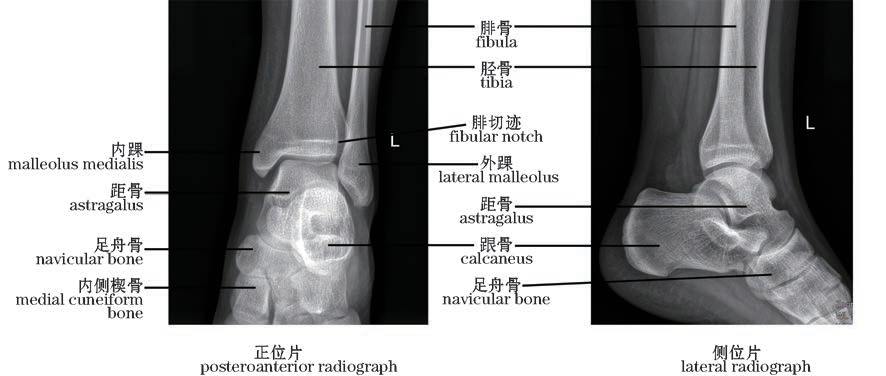

图2-60 踝关节X线片(左)

The ankle joint,X-rays(left)